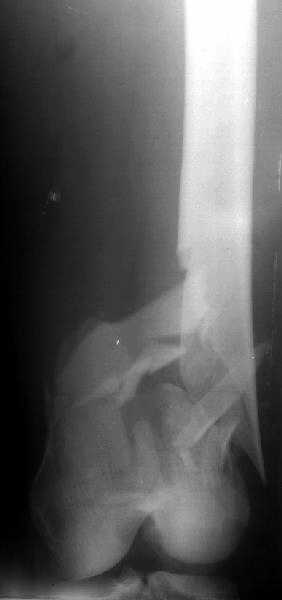

1

In the supracondylar nail system both the ends are lockable by jig and no free hand technique is needed.

I do not see the proximal bolts; I presume they must be at he trochanter level. In a supracondylar nail you are able to see both side bolts in one picture. ( Enclosure)